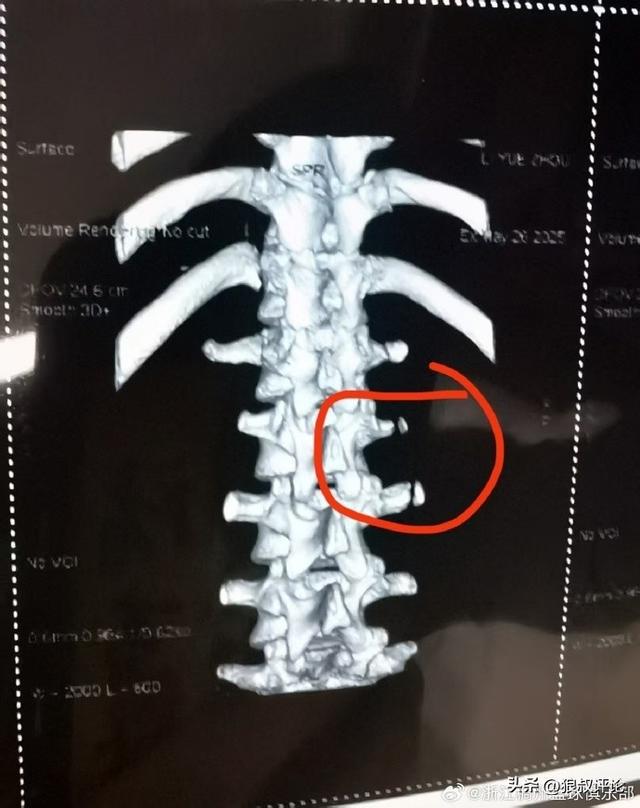

北京时间6月9日,根据浙江男篮官方社交媒体发文:我俱乐部球员李悦洲在5月26日秦皇岛备战U19世青赛训练中不幸遭遇横突骨折,经中国篮协联系北京积水潭医院骨科专家会诊,预计伤停3个月。